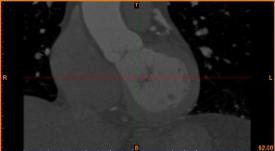

首先通過(guò)病人的心臟冠脈造影CT數(shù)據(jù),獲取病人的心臟冠脈三維模型。

病人的冠脈造影CT數(shù)據(jù) 提取出的冠脈三維數(shù)據(jù)